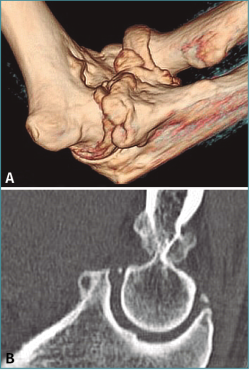

En todos los casos hemos solicitado una tomografía axial computarizada (TAC) 3D previa a la intervención, lo que es de gran utilidad para preparar la cirugía y saber dónde y cuántos osteofitos y cuerpos libres vamos a resecar (Figuras 1 y 2; Vídeo, minutos 0-1:36).

Figura 1. A: tomografía axial computarizada bidimensional (TAC); B: TAC 3D para valorar la presencia, el tamaño y la localización de osteofitos y cuerpos libres.

Figura 9. Caso 6. Corte de tomografía axial computarizada (TAC) de un paciente con rigidez postraumática con fractura osteocondral de cabeza radial y cóndilo humeral lateral.